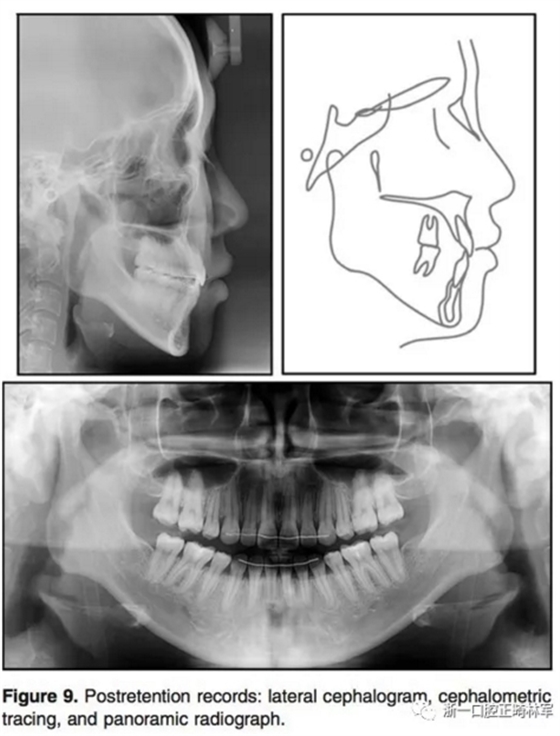

1年的保持,示咬合和面型保持良好。治療后和保持后的重疊像示上下切牙輕微唇傾,導(dǎo)致覆蓋有所增加。上下第一磨牙的位置變化微乎其微。